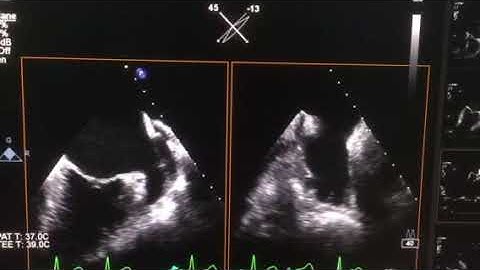

Left Atrial Appendage: 3D GlassVue Assessment